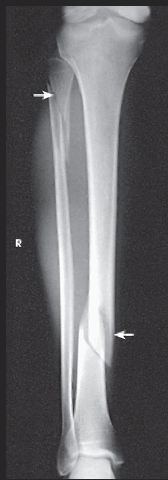

Name this projection.

AP leg (tib fib)

What SID is used?

48 inches

What anatomy is placed parallel to the IR?

Patella and femoral condyles

What position is the patient in?

Supine w/ foot dorsiflexed

What anatomy must be included on the radiograph?

Entire tibia and fibula plus adjacent joints

What should be done if the entire tib/fib cannot fit on the IR?

Either rotate the IR to be diagonal to the leg OR take two separate images (a bigger image of whichever joint is more in pain and a smaller image of the other joint)

How far beyond the adjacent joints should you see light?

1.5"

What part of the tib/fib should be free of superimposition?

Fibula midshaft